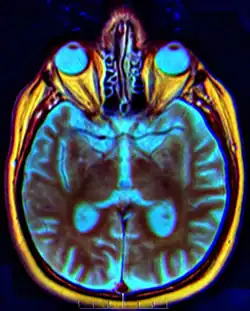

El quiasma óptico (del gr. χίασμα, -ατος, disposición cruzada, como la de la letra χ) es la parte del cerebro donde se entrecruzan parcialmente las fibras axónicas de los nervios ópticos[1] Es una estructura en forma ovalada que constituye el punto de unión entre el nervio óptico del ojo derecho y el nervio óptico del ojo izquierdo. Esta estructura mide aproximadamente 12 milímetros de ancho, 8 milímetros de largo y unos 4 milímetros de alto y se encuentra situada en la base del cerebro a unos 5 o 10 milímetros de la glándula hipofisaria. En este entrecruzamiento la mitad de las fibras pasan del nervio óptico derecho a la cintilla óptica izquierda, y viceversa. El quiasma óptico está situado en la fosa cerebral anterior, por delante de la silla turca.

Las imágenes formadas en cada una de las retinas se cruzan al lado opuesto del cerebro en el quiasma óptico. Esto permite que las imágenes de cada lado del campo de ambos ojos se transmitan al lado apropiado del cerebro. Luego del quiasma óptico, los nervios ópticos pasan a llamarse cintillas ópticas.